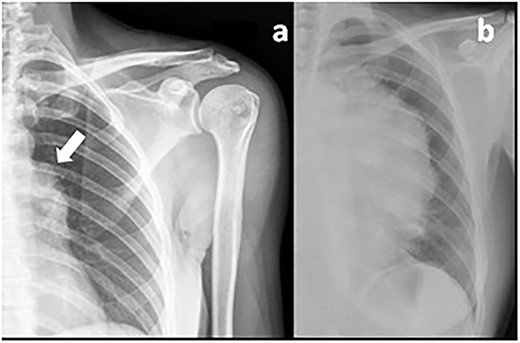

The curious aspect of this clinical case reminds us of the importance of a systematic and global look of the imaging scans. Years before the thymoma diagnosis, the patient underwent a shoulder X-ray (Fig. 1) due to localized musculoskeletal pain. In this image, an irregular shape of the aortic arch was visible, probably related to the growing mediastinal mass. An earlier diagnosis would perhaps allow a complete mass resection without such extensive surgery and less morbidity for the patient.

Previous shoulder X-ray (a) showing an irregular shape of the aortic arch (arrow) probably related to the mediastinal mass in comparison with a recent chest X-ray (b) showing the giant thymoma.